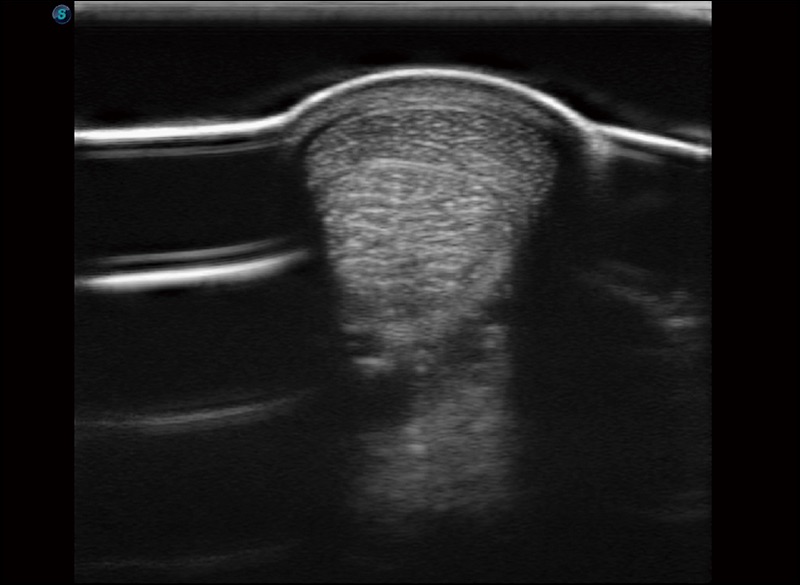

α1卓越的图像质量和便捷的工作流程,使每位宠物医生都能轻松扫查。其全面的兽用应用功能和紧凑型的结构设计,可以满足动物检查的多种需要。专业的预设检查模式和多领域测量软件包有助于为不同类型的动物提供检查, 让宠物医生能够出色的完成工作。

穿刺针增强

高清显示穿刺进针情况